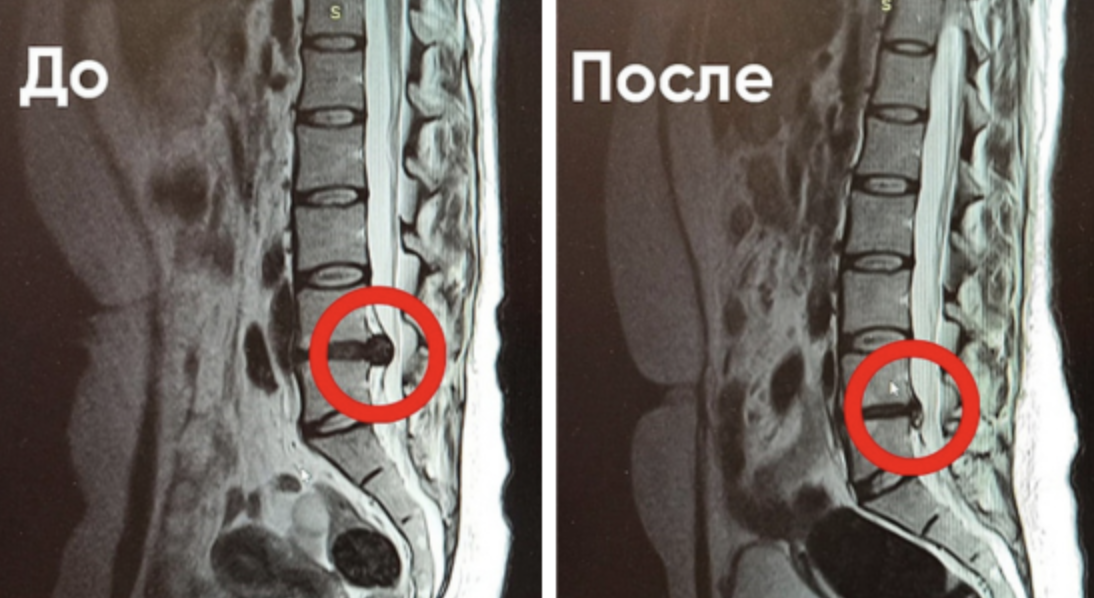

результат безоперационного лечения межпозвонковой грыжи в "Ноосфере"